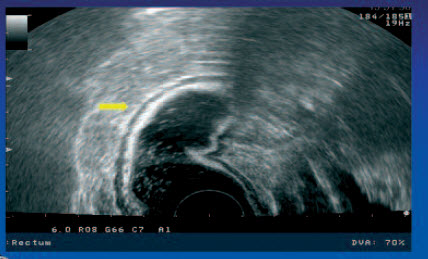

Normální nález stěny rekta

Postižení stěny konečníku